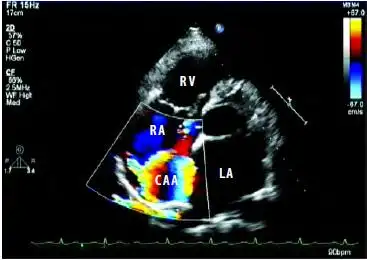

【共享】冠状动脉—右室瘘 - 超声医学讨论版 -丁香园论坛

彩色多普勒超声诊断右冠状动脉右房瘘合并右房内冠状动脉瘤1例